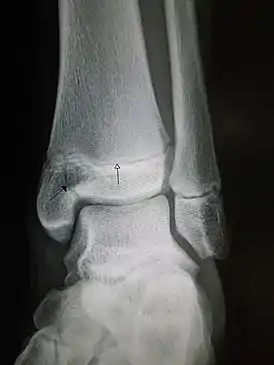

![]() Рентгеновский снимок голеностопного сустава с эпифизеолизом медиальной лодыжки. Черная стрелка - линия перелома, белая указывает на ростковую зону. | |